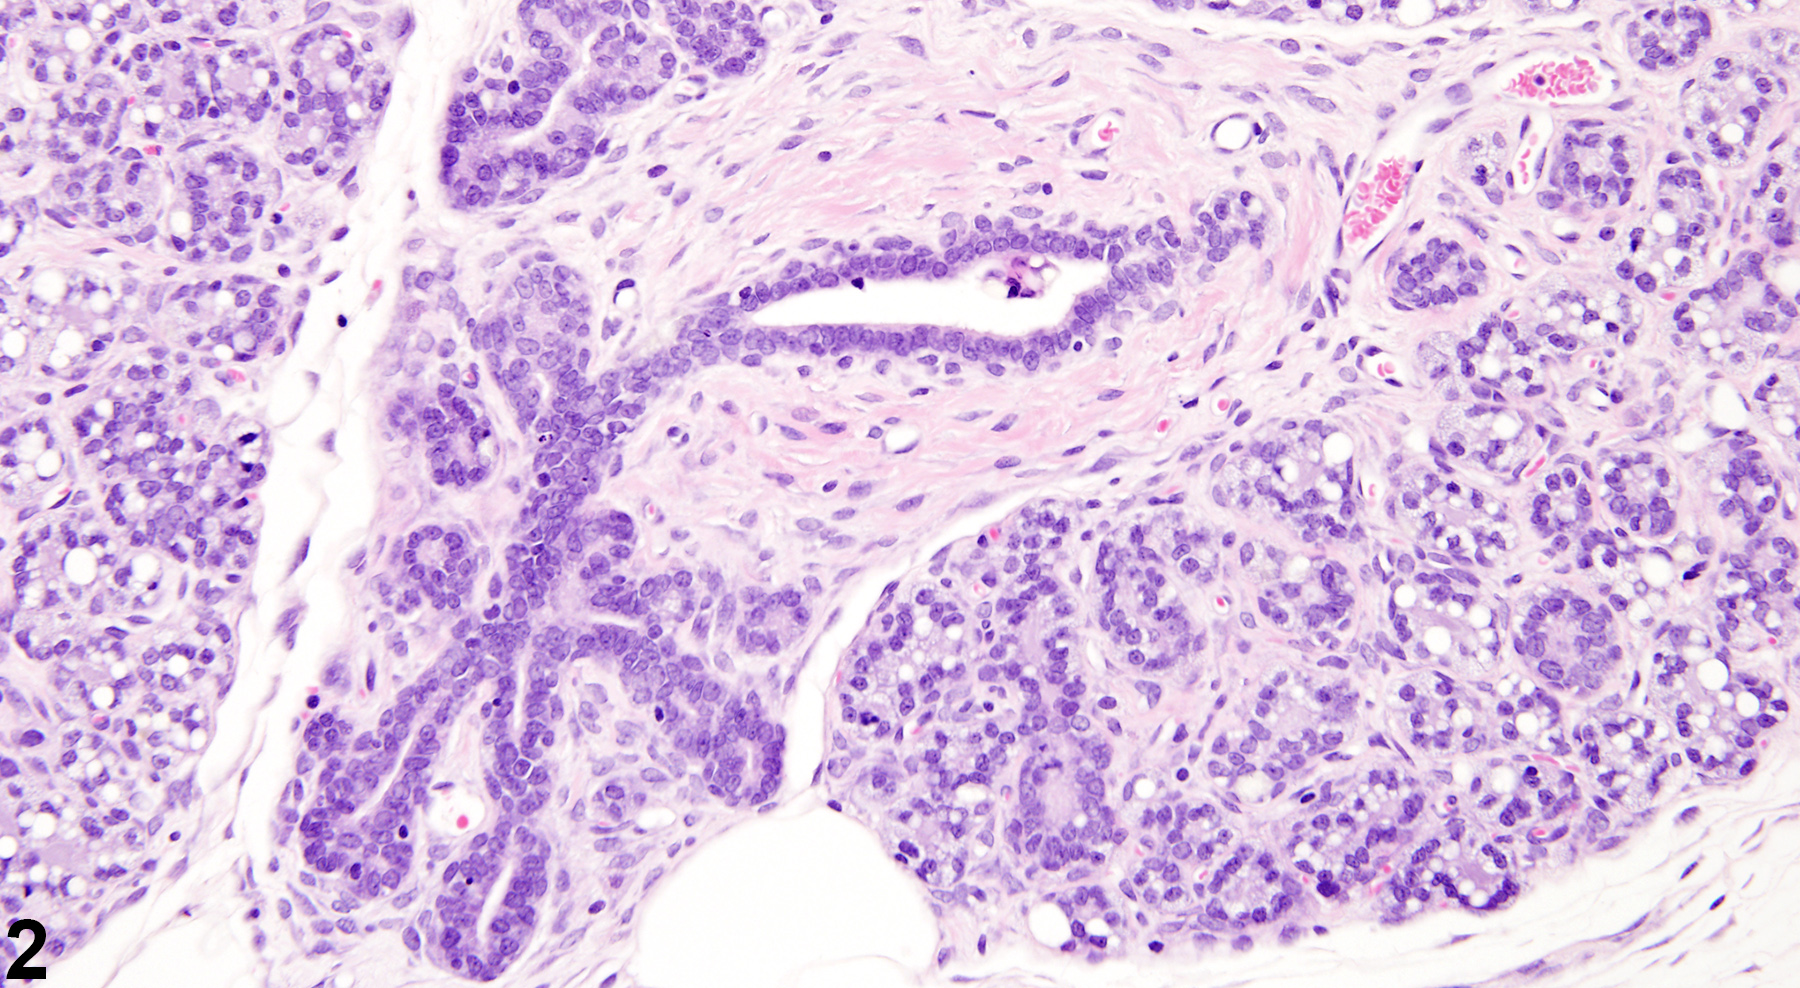

Nonphysiological, spontaneously occurring mammary gland hyperplasia of uncertain etiology is a common aging change in virgin rats and mice, and can occur in both sexes. Mammary gland hyperplasia can also result from ovarian or pituitary hormone imbalances, which can be primarily or secondarily induced by factors such as exogenous toxins and nutrient deficiencies. Hyperplasia can also be a precursor to mammary gland neoplasia (spontaneous or treatment-related). Lobular hyperplasia (Figure 1 and Figure 2) can be focal or diffuse and is characterized by enlarged lobules with increased numbers of relatively normal alveoli. Ducts are typically not affected. Depending on the amount of intraluminal secretions, the affected alveoli may have a variable diameter but are lined by a single layer of well-differentiated cells. Reactive fibrous stroma is usually present, with amounts ranging from rather scanty to more extensive. However, the lack of both compression and a prominent collagenous stroma are features that distinguish lobular hyperplasia from fibroadenoma. As well as being a treatment-related or aging change, lobular hyperplasia in females can be a physiological change occurring during pregnancy and lactation, a result of xenobiotics that cause hyperprolactinemia, as well as in pseudopregnant animals. Lobular (alveolar) hyperplasia may be a precursor of adenoma, fibroadenoma, or adenocarcinoma. However, chemically induced hyperplastic lobules do not appear to be precursors to adenocarcinoma.

Mammary gland - Hyperplasia, Lobular in a female F344/N rat from a chronic study. There are multiple enlarged lobules with increased numbers of alveoli in the mammary gland.